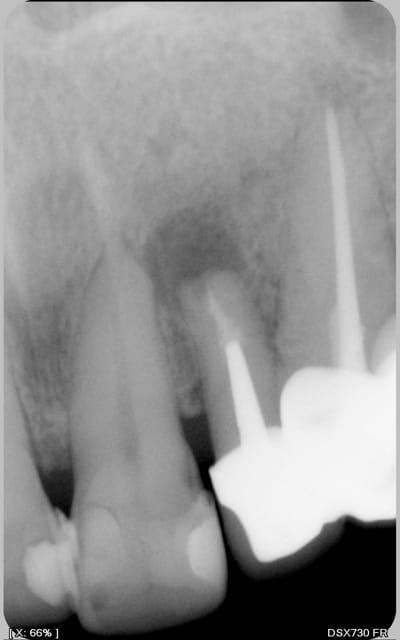

Cette patiente se plaint d'une lourdeur sur sa 21.

Les tests de vitalité sur 21 et 11 sont positifs et similaires et aucune reponse a la percussion

Est'il normal que dix ans aprés sa résection de 22, une telle image soit encore visible.

Une infection par des canaux latéraux de 21 est'elle possible

tenteriez vous quelque chose a rétro, en sachant que 22 est solidaire de 23, qui est pilier de bridge 24/25 inters, 26 couronnée

Je pense que le " réservoir" de germes est endocanalaire et que sans reprise complète du traitement endo, on ne pourra pas avancer. Donc dépose du bridge et reprise de tout le traitement endo & proth. (apex de 23 pas net...), après temporisation nécessaire, il faut réévaluer 21.

Mais on peut aussi prendre en considération que si la prothèse semble bonne au plan esthétique et fonctionnel, vu qu'il s'agit d'une dent d'accès plutot facile et que la destruction osseuse est déjà présente, une chirurgie avec nettoyage et obturation a rétro du canal jusqu'au tenon est envisageable.

Cette 22 est pour moi condamnée a moyen terme (racine trop courte)

Faire une chir toute seule dans ce cas reviendrait à se trouver presque au niveau du tenon avec pas forcement 3mm d'hauteur d'obturation .

A coté de ca la hauteur de la racine residuelle serait franchement trop courte pour tenir le coup mécaniquement.